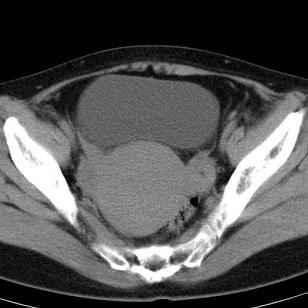

标题: CT19559:子宫及附件正常吗?

女,35岁,反复下腹部隐痛数月。

感觉上,子宫好象大了点

如果未孕,子宫体稍大,宫腔增宽,附件区未见异常密度影,还是建议结合b超检查为好,ct平扫对妇科没有优势。

子宫弥漫性等密度肿大,宫腔内缘见结节影突入腔内,子宫内膜异位可能